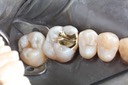

Ted Kanamori #14 pre-op

Ted Kanamori #14 amalgam removal